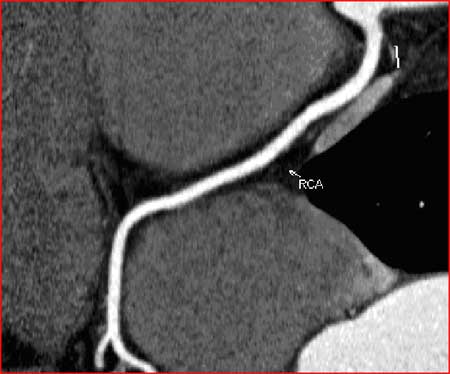

Normal Right Coronary Artery